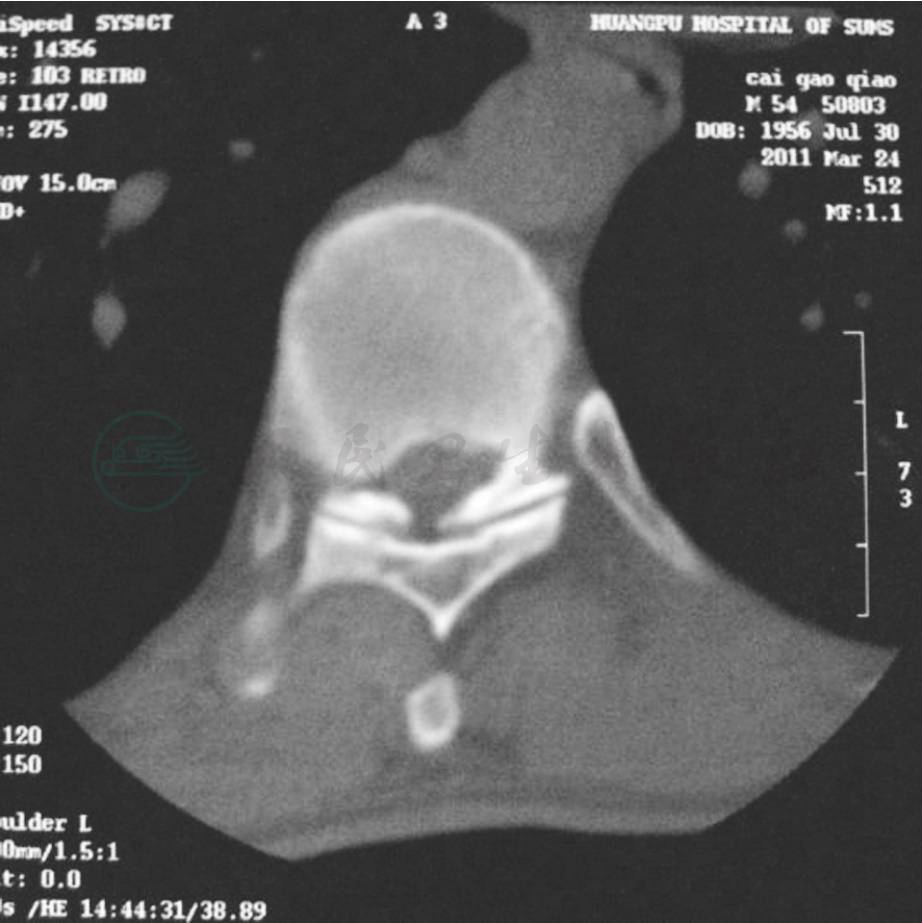

1.关节突关节增生、肥大、内聚,使椎管横截面积变小,呈不规则的三角形,甚至呈三叶草样改变,在椎管的侧后方压迫脊髓(图1)。

图1 退变性胸椎管狭窄

CT扫描部位要准确,必要时需薄层扫描,范围要适当、足够,否则易漏诊。CT扫描可清楚地显示胸椎管狭窄的程度和椎管各壁的改变。椎管后外侧壁即椎板下缘、关节突前内侧的单侧或双侧板状或结节状骨化块突入椎管内。后纵韧带骨化和关节突肥大可加剧椎管狭窄。严重时,椎管呈三叶草或窄菱形。横断面上,压迫重的地方脊髓变细,关节突关节和骨化后纵韧带密度增加(图1,图2)。